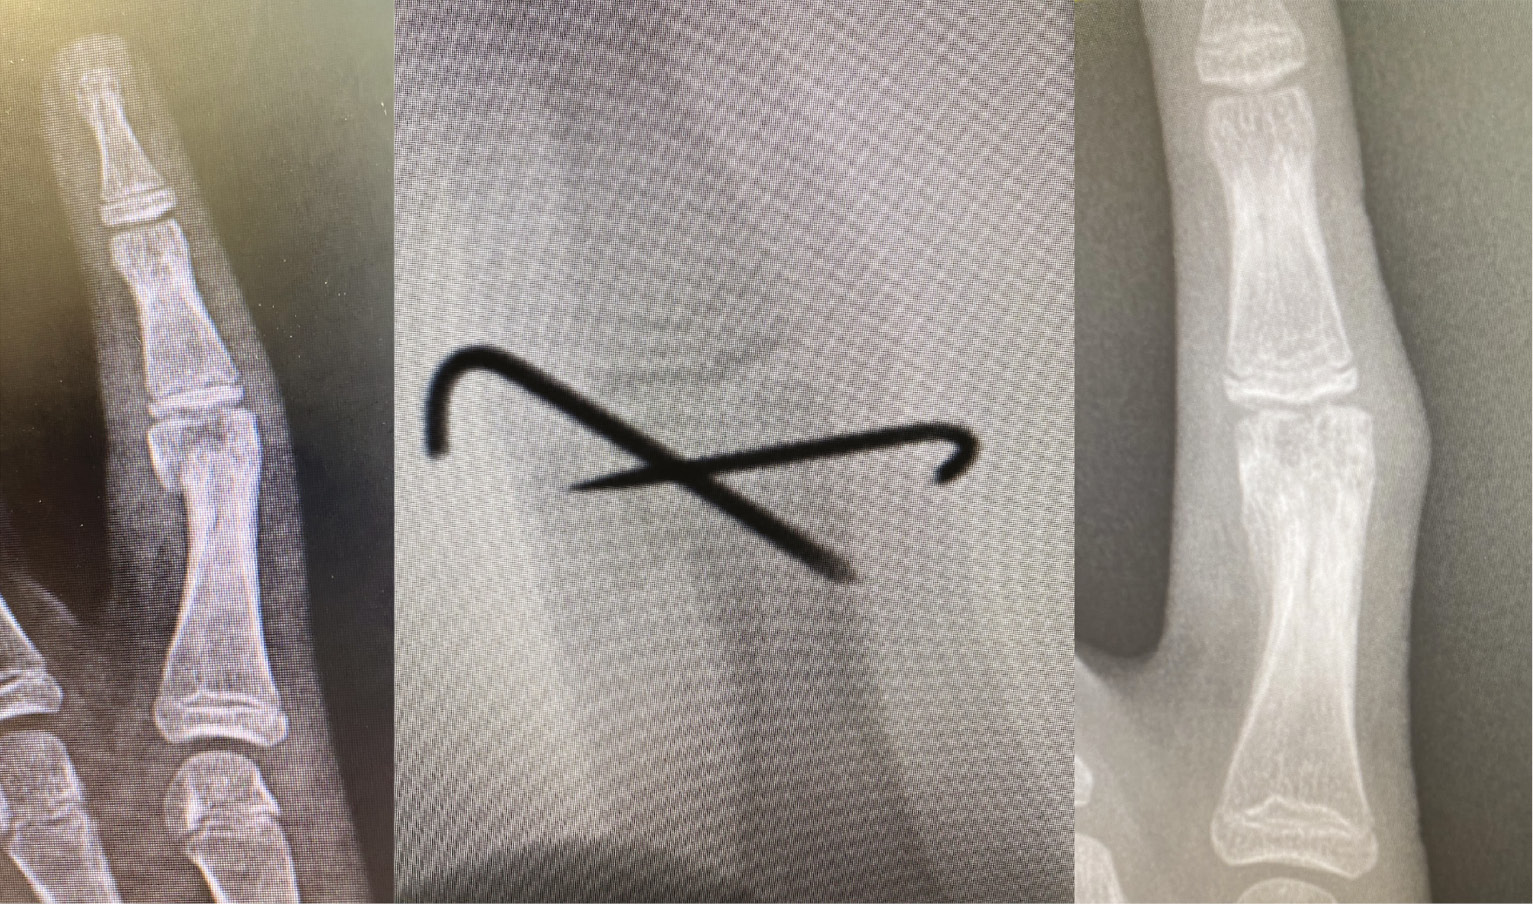

The incidence of pediatric phalangeal fractures spikes in early adolescence and corresponds with initiation of participation in contact sports.54 Salter-Harris type II fractures of the proximal phalanx are the most common type of phalangeal injury in children due to the intrinsic weakness of the physis compared to its surrounding structures.54 Surgical treatment is indicated for displaced intraarticular or unstable fractures (Figure 13).

Figure 13. A 7-year-old with an intraarticular fracture that required closed reduction and percutaneous reduction and pinning.

In the operating room, closed reduction is attempted. If successful, stability is then assessed by ranging the finger. If the fracture is determined to be unstable, percutaneous fixation can be achieved through two 0.9 mm K-wires, one ulnar and one radial, that are run in an antegrade and crossed fashion. Patients are subsequently casted.55 Wires can also be used to osteotomize or reduce phalangeal neck fractures (Figure 14).

Figure 14. This 5-year-old sustained a phalangeal neck fracture 10 days prior to clinic appointment. The fracture was partially healed and closed reduction in the OR was not possible. He underwent percutaneous leveraging of the fracture and stabilization with dorsal buttress pin.